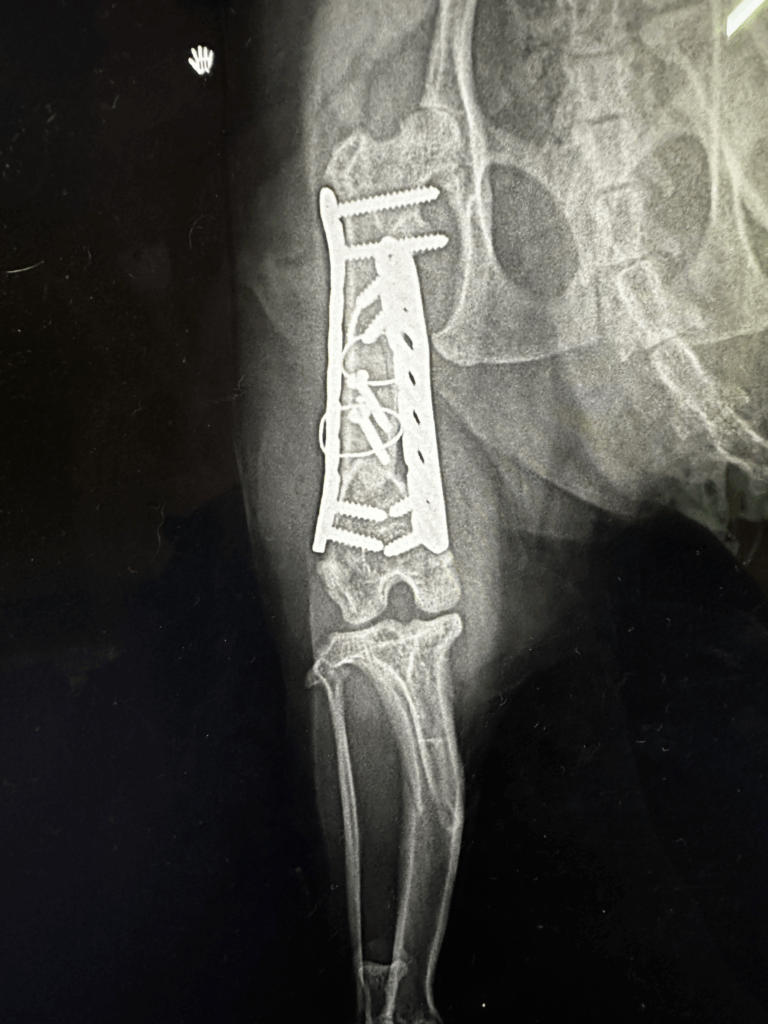

自宅のキャットタワーから転落してしまい、大腿骨が骨折しました。当院へ来院。

整形外科専門外来でプレート固定術を行ったところ、現在は元気に走り回れるようになりました。

一方で、一次病院で誤った治療を受けてしまい、骨が曲がったまま固まってしまったケースもよくあります。この場合は再手術が必要となり、猫にも飼い主さんにも大きな負担となります。

レントゲンだけでなく、必要に応じてCT撮影を行い、骨折の状態を立体的に把握できます。 - 専用の手術器具とインプラント

プレート、スクリュー、ピンなど、その子に合わせた最適な固定方法を選択可能。 - 経験豊富な整形外科医

骨の角度、固定の強度、将来の歩行能力を見越した治療を実施。 - 術後管理が徹底